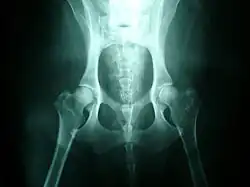

Normal hips, for comparison

Hip dysplasia is diagnosed with radiographs of the pelvis. It is also common to X-ray the spine and legs, as well as the hips, since soft tissues can be affected by the extra strain of a dysplastic hip, or there may be other undetected factors such as neurological issues (e.g. nerve damage) involved.